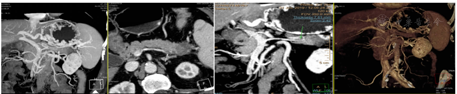

上腹部CT增强示(图2):(1)胰尾部占位性,考虑新生物可能,侵润脾动脉;脾静脉细小,近脾门段腔内充盈缺损,提示瘤栓形成可能;胃底周围静脉曲张,与门静脉左支侧支循环形成;(2)少量腹水。上腹部CTV示:胰尾部占位,成渐进性延迟强化,考虑恶性肿瘤性病变,胰腺Ca可能,脾静脉受侵、瘤栓形成;致脾静脉回流受阻、继发性脾大,脾门区静脉、胃体底静脉、胃网膜静脉、胃短静脉及胃冠状静脉曲张(以胃底体静脉曲张为著),胃冠状静脉与门静脉左支交通,综合上述考虑胰源性门静脉高压(脾-胃-门静脉分流)。